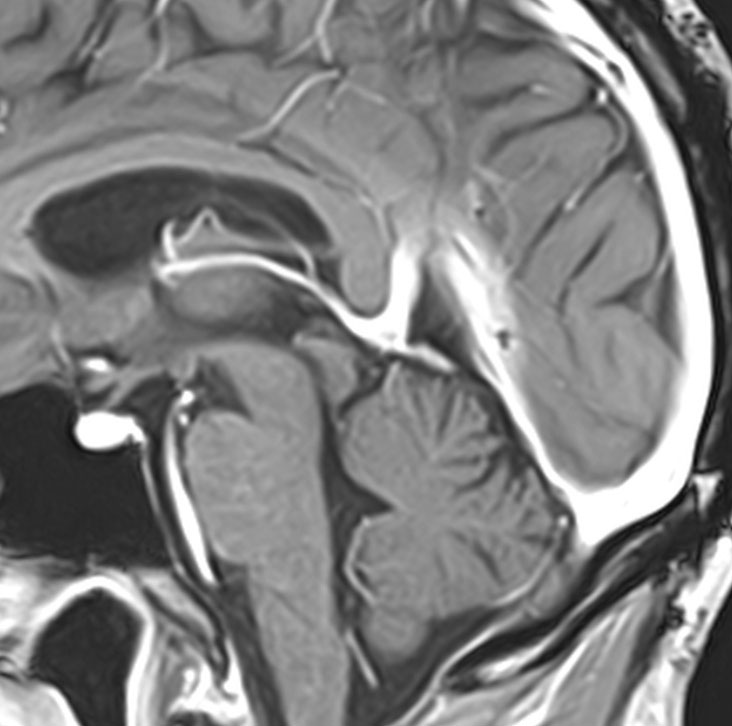

30代の女性に発生した髄膜腫です,一見すると松果体細胞腫と見分けはつきません。右の画像に見られるように典型的な中脳水道狭窄を生じていました。

軽度の閉塞性水頭症もありますが,頭痛も無く無症状なので経過を観察しました。髄膜腫だと診断できるのは,右の画像で見られるようにガレン大静脈が右側に偏っているからです。松果体細胞腫の場合は,ガレン大静脈は上方に変位します。

1年間経過観察したら水頭症が進行して脳室が拡大,腫瘍のサイズも大きくなりました。右側の画像で見られるようにガレン大静脈の左側のテントの下面から発生した髄膜腫でした。

左は手術直後の画像です,手術は左側のテント下面を見るために,後頭部経テント法 OTA occipital transtentorial approach で,小脳テントの左側を切断して腫瘍を全摘出しました。右側は6年後の画像ですが,腫瘍再発はありません。